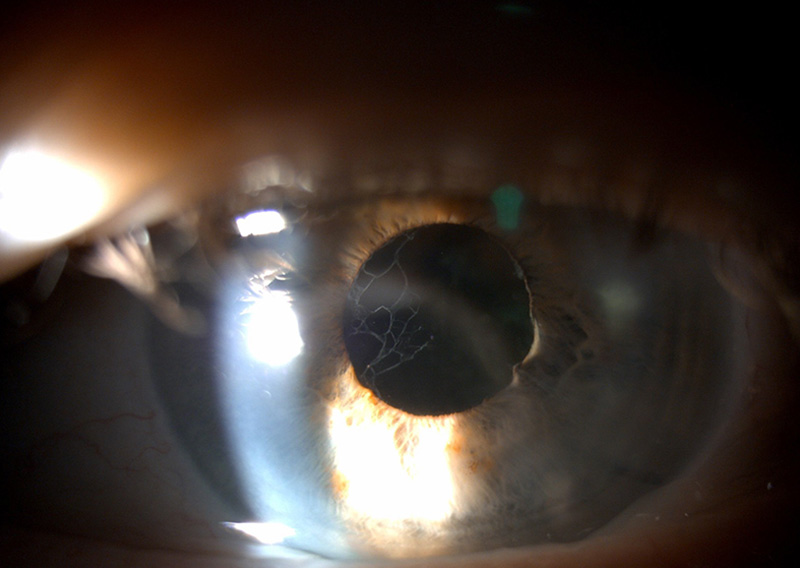

Refracting after a Vivity IOL is different than a regular refraction.